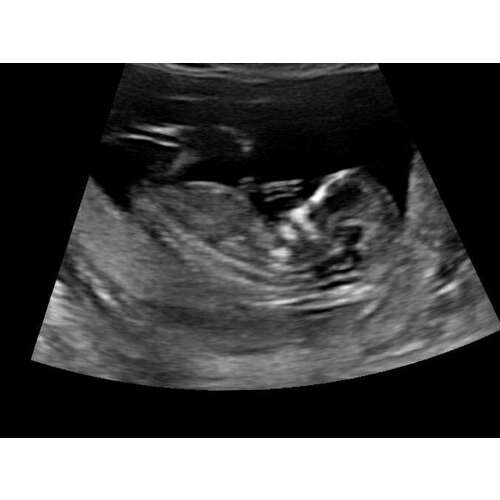

Iemand een idee. Dit was bij 12+5